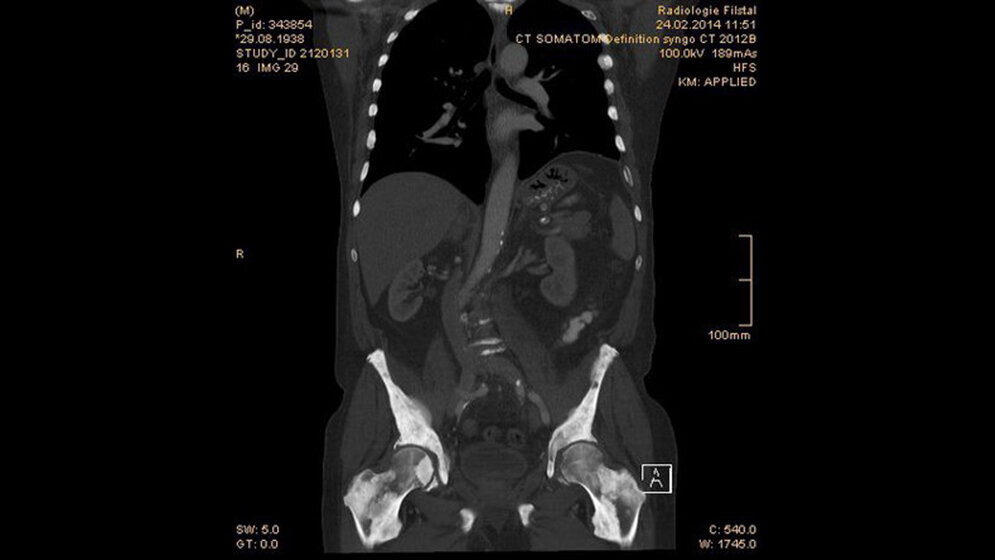

Abb. 1.3: die koronale 2D-Rekonstruktion zeigt auch im Bereich der proximalen Femoren die diffuse ossäre Metastasierung

Das Prostatakarzinom ist die zweithäufi gste Ursache der krebsbeding-ten Todesfälle bei Männern. Die Metastasen sind hauptsächlich os-teosklerotisch und durch exzessive Osteoblastenaktivität verursacht. Die Diagnose wird durch klinische, biochemische und histologische Untersuchungen gestellt. Die bildgebende Diagnostik hat eine Be-deutung für das Staging.